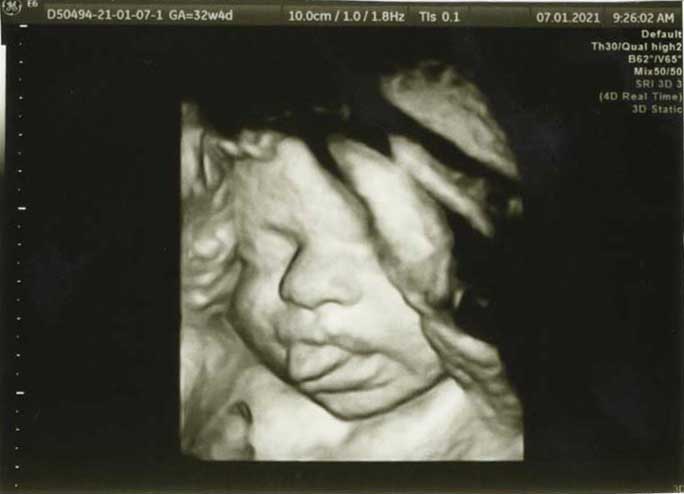

3D/4D HD LIVE

Στο ιατρείο μας προσφέρουμε υψηλής ευκρίνειας 3D και 4D τεχνολογία απεικόνισης του εμβρύου. Η τεχνολογία αυτή αποτελεί ένα ακόμα σημαντικό διαγνωστικό όπλο στη φαρέτρα του προγεννητικού ελέγχου, ενώ ταυτόχρονα ενισχύει την ανάπτυξη του δεσμού ανάμεσα στους μελλοντικούς γονείς και το μωρό τους.